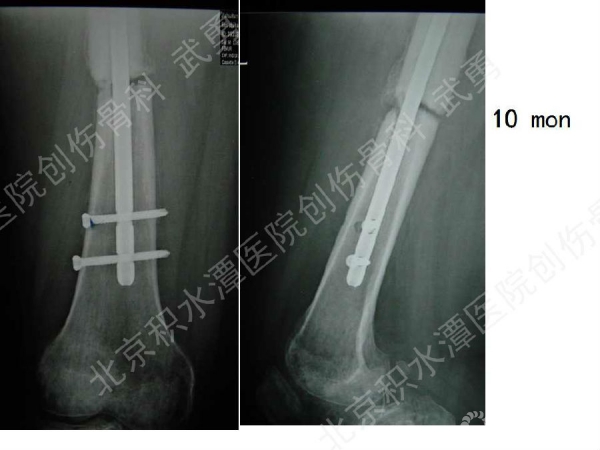

髓内钉骨不连的类型:增生型、萎缩型

病例分析:

髓内钉骨不连的治疗: